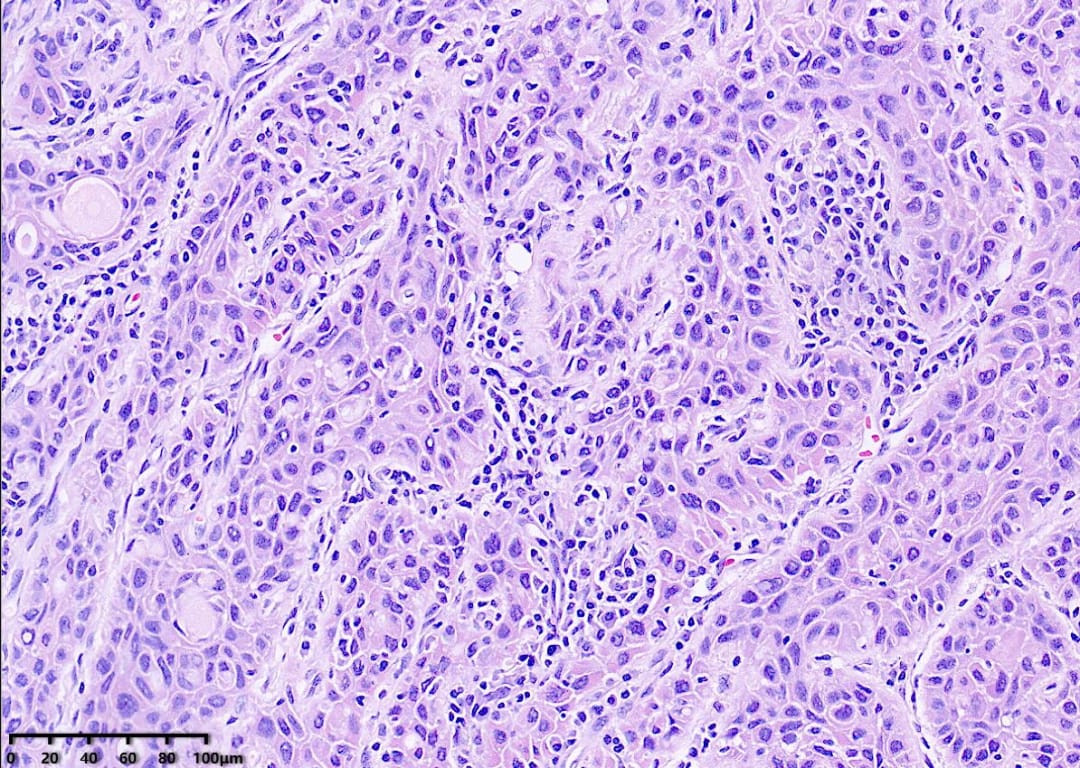

肿瘤组织呈条索状、巢团状、实片状结构排列,间质淋巴细胞浸润

高倍镜,肿瘤细胞胞浆丰富,嗜酸性,可见细胞间桥,核深染,核分裂可见

镜下可见肿瘤细胞呈实性巢状、条索状排列,部分癌巢周边细胞呈栅栏状排列,可见细胞间桥、角化珠和单个细胞角化。肿瘤细胞胞质嗜酸性,核深染,核分裂象多见。间质常伴有纤维组织增生和淋巴细胞浸润。免疫表型上,肿瘤细胞通常表达PAX8、CK19、CK-H、TTF-1、CyclinD1,以及鳞状细胞标记物CK5/6、p40、p63。大部分病例可检测到BRAF V600E突变。分子遗传学方面,TP53及BRAF V600E突变是甲状腺鳞状细胞癌的常见特征。